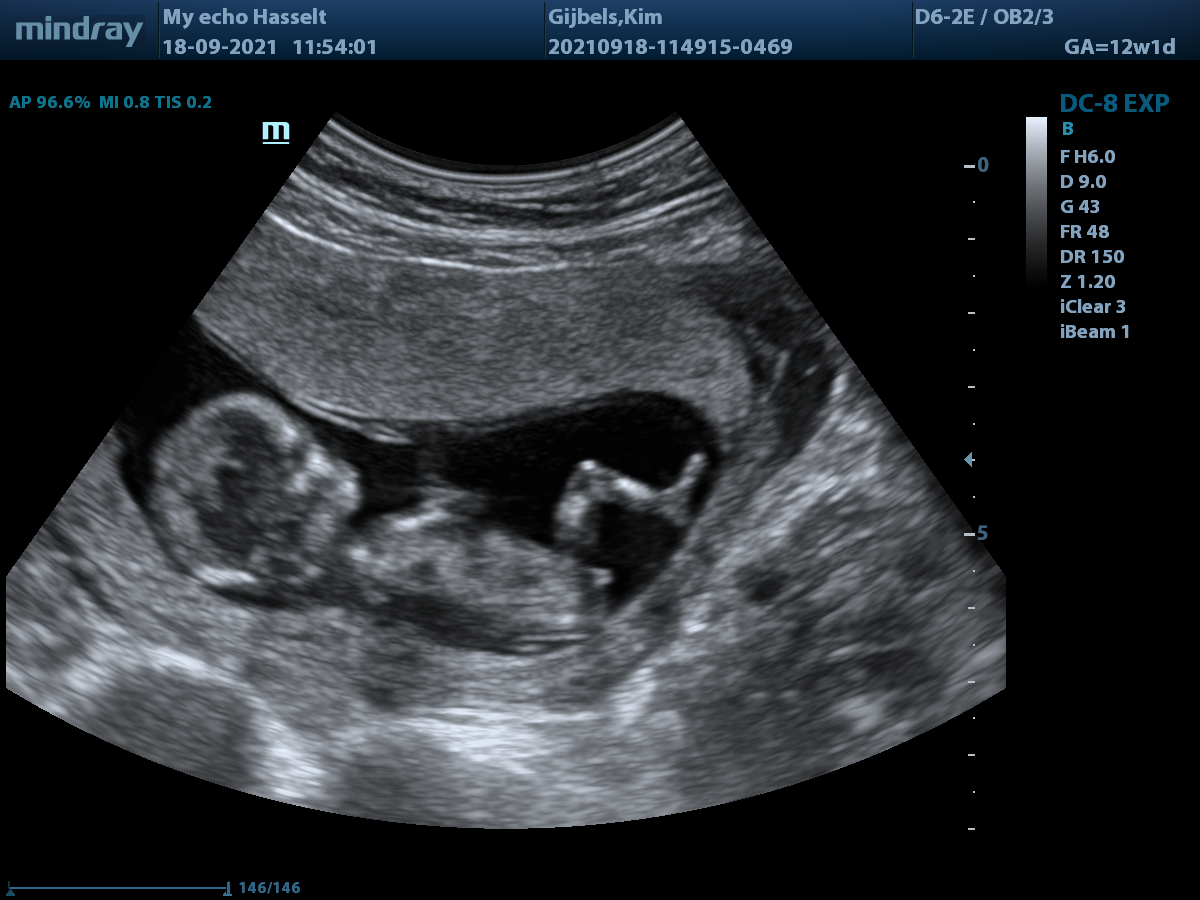

Dankzij het optreden van mijn psychologe, die het ware verhaal van het ontstaan van de zwangerschap in mijn medisch dossier van Genk liet schrijven, verliepen de echo’s sindsdien met heel wat minder psychisch ongemak. Zelfs de vroedvrouw aan de balie was bij de 12 weken echo helemaal op de hoogte waardoor er eindelijk niet zo luchtig meer gedaan werd over alles.

Een paar uur later was het zover, ze zouden wat stalen nemen van de placenta om te achterhalen of dat het kindje gezond was. Nadat ze met een echo de ligging van de placenta bepaald hadden maakte ze met hun drieën (2 gynaecologen en een vroedvrouw) alles klaar. Na de buik grondig ontsmet te hebben en de steriele doeken te leggen kreeg ik een lokale verdoving in de buik toegediend (dat voel je wel even) en even later werd onder begeleiding van het echotoestel de naald in mijn buik geduwd. Gelukkig bleef het ongemak wel beperkt, al voelde ik het wel duidelijk wanneer ze door de baarmoeder heen was (dat voelde als iets heel stug). Van het op en neer bewegen van de naald heb ik eigenlijk gelukkig niets gevoeld. Wat wel wat eng was, dat die naald de hele placenta doorkruiste iedere keer met de beweging en ons kindje niet ver eronder wat aan het prullen was met haar handjes. (jawel, het is haar ;-))

De zaterdag vlak voor de vlokkentest hadden we nog een 2D pretecho, daarop had ik al gezien dat de kans groot was dat het een meisje was (nub theorie) en dus zocht ik online al een haakpatroon voor een babykleedje (allereerste keer kledij gehaakt en trots!) en nog maar een regenboogdekentje, want alhoewel ik verschrikkelijk angstig was dat dit mis zou lopen, had ik ook wel hoop.